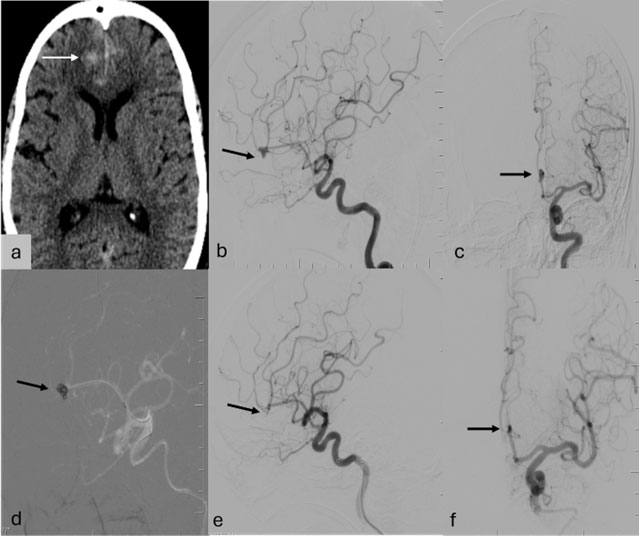

A 75-year-old woman presented with transient bilateral blurring of vision. Ophthalmic evaluation was normal. MRI brain and orbits revealed bilateral supraclinoid ICA saccular aneurysms—larger on the left (11 × 8.5 mm) and a smaller right-sided aneurysm (3 × 2.5 mm) (Fig. 3a).

Given the size and potential mass effect of the left ICA aneurysm, DSA and endovascular treatment were planned. The aneurysm had a wide neck (Fig 3b, c); therefore, a flow diverter (Surpass Evolve 4.5 × 25 mm, Stryker) was deployed across the aneurysm neck, with distal landing in the terminal ICA and proximal landing in the horizontal cavernous segment (Fig. 3d, e). She recovered well and was discharged on Day 2 without any neurological deficits. Follow-up imaging is scheduled at 6 months to assess aneurysm occlusion and device patency.

Figure 3: (a) MR angiogram MIP image showing bilateral ICA aneurysms (black arrows) (b, c) DSA Left ICA angiogram frontal and lateral projections showing saccular aneurysm in the clinoidal and paraophthalmic segment of left ICA (black arrow) (d) Fluoroscopic spot image showing the flow diverter (FD) with optimal opening (black arrowheads) (e) Post FD placement angiogram showing stasis within the aneurysm sac (black arrow).